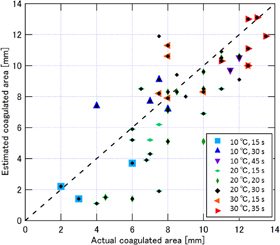

Examples of real-time LMI images are shown in Fig. 10. Maps of tissue displacement and normalized displacement are shown in Figs. 10(a) and 10(b), respectively. In this case, on-line LMI images were updated before the start of the next data acquisition. Simultaneously, the times for calculation including data transfer and displaying LMI were measured in each step; the results are shown in Fig. 11. The average and maximum calculation times were approximately 600 and 850 ms, respectively.

Fig. 10. LMI maps of real-time measurement (L = 20 mm, 20 °C, 20 s ablation).